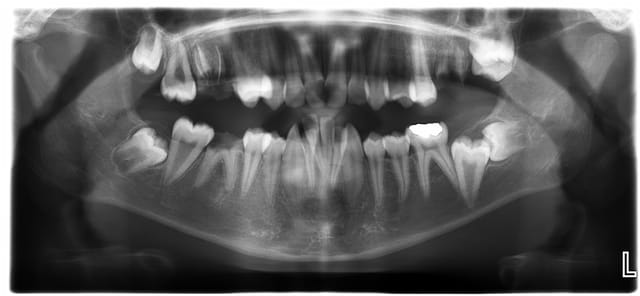

Patient de 15 ans, pour lequel le collège a pris directement rdv avec moi ...

Outre les soins dentaires que je vais gérer, il y a les malpositions... et là, çà va être chaud : il est CMU et je ne suis pas sûre d'arriver à avoir un bon suivi ...

Je me suis déjà occupée de 11/21 mais après, est-ce qu'il reviendra quand l'esthétique sera résolu ???